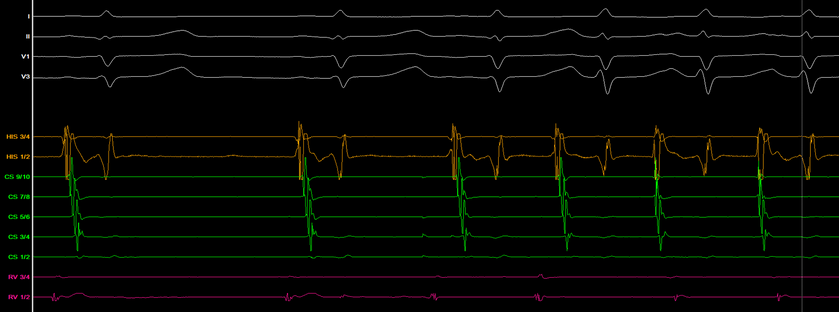

Baseline ECG/EGM

Tachycardia characteristics

-

Long RP tachycardia with midline activation

TCL 450ms

VA interval 184ms